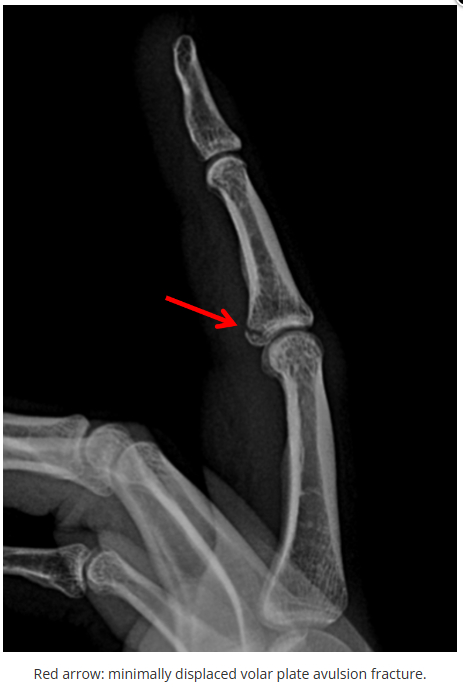

今天是腕部与手的X线片。所有X线片都

带有标注和说明

,可以选择长按图片,

自动翻译相关说明

。

进阶篇